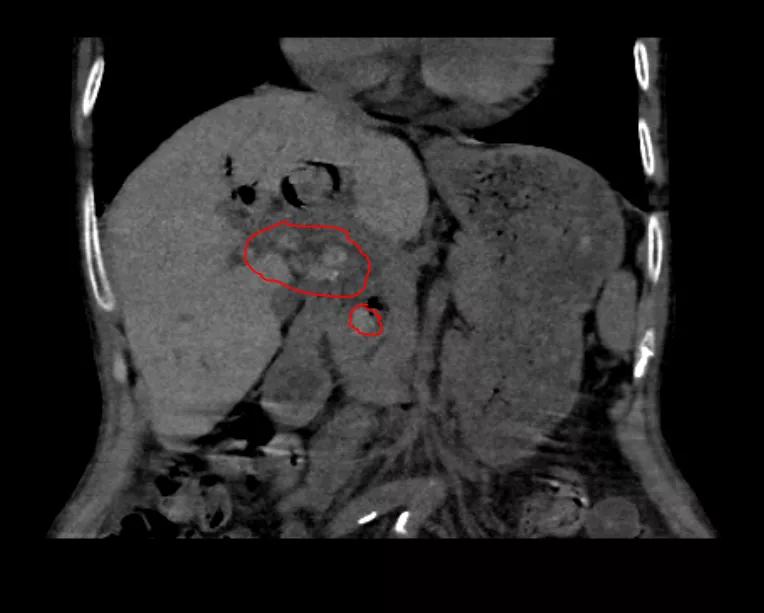

胆总管结石及肝内胆管多发结石(术前)

术中我科应用腹腔镜+硬质胆道镜经胆总管碎取胆总管结石及肝内胆管结石。

术后结石清除,胆管扩张减轻

术中一次性取净胆道结石,避免了结石残留,大大降低了短期内结石梗阻的复发几率,从而避免了再次手术的创伤打击,真正达到了微创手术的目的。